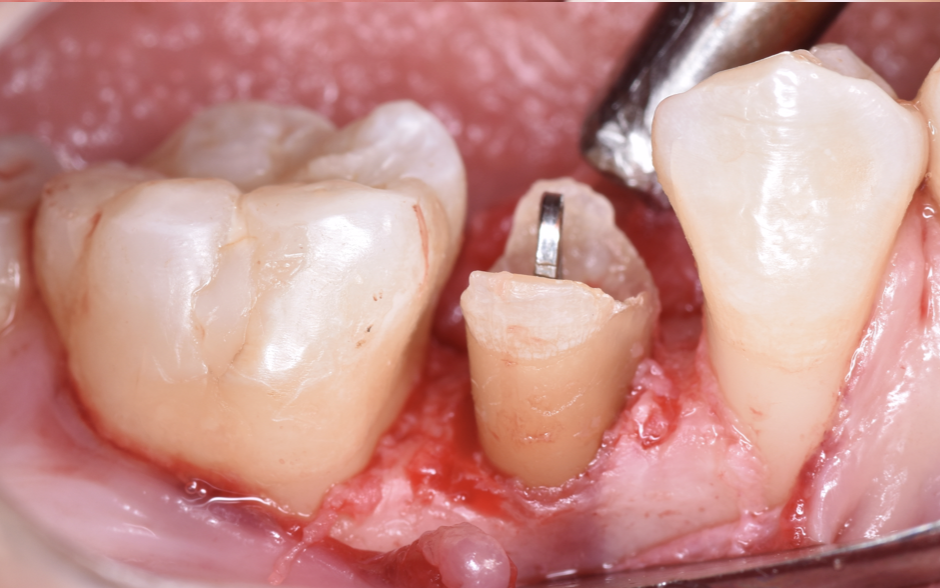

治療後

クラウンレングスニングとは、被せ物を安定して装着するために、歯ぐきや骨の位置を整えて歯の見える部分(歯冠)を長くする外科的処置のことです。

簡単に言うと、「歯ぐきに埋もれて見えない部分の歯を、見えるように出してあげる処置」です。

クラウンレングスニングを行うことで、被せ物のためのスペースと清掃しやすい環境を確保でき、再治療のリスクが大幅に減ります。